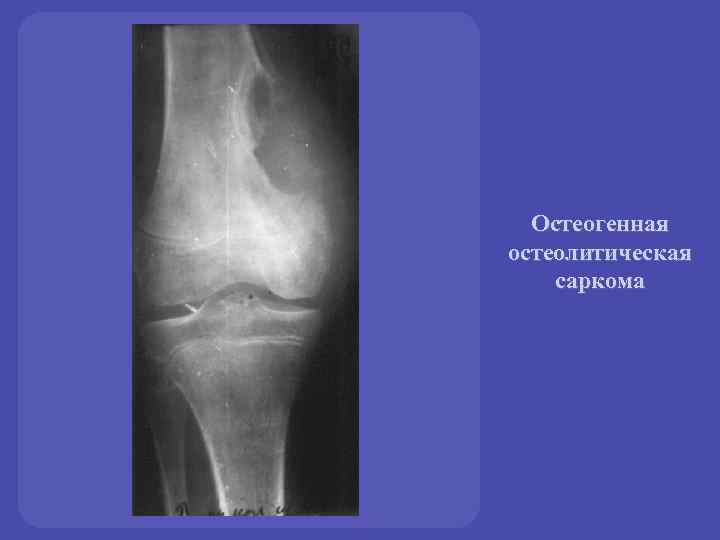

Остеосаркома коленного сустава: информация и поддержка

Раздел: Необычные решения